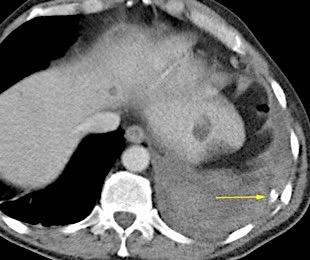

Hidronefrosis con cálculo ureteral

Obstrucción…21 aguda con cálculo e hidronefrosis..12

Freitas A et al. Pleural Effusion Secondary to Obstructive Uropathy: A Case of Urinothorax. Eur J Case Rep Intern Med. 2020/ Toubes ME et al. Urinothorax: a systematic review. J Thorac Dis 2017;